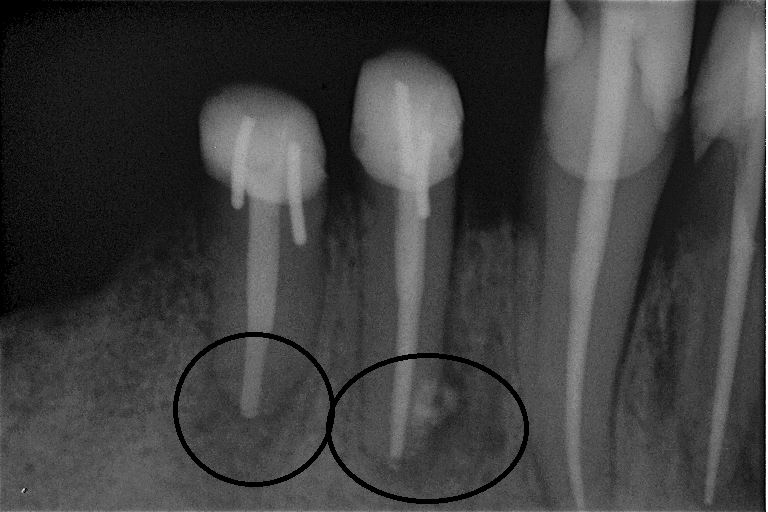

Fallbeispiel für eine große Entzündung an der Wurzel

Wurzel nach erfolgreicher Behandlung 2 Monate später schon fast ausgeheilt